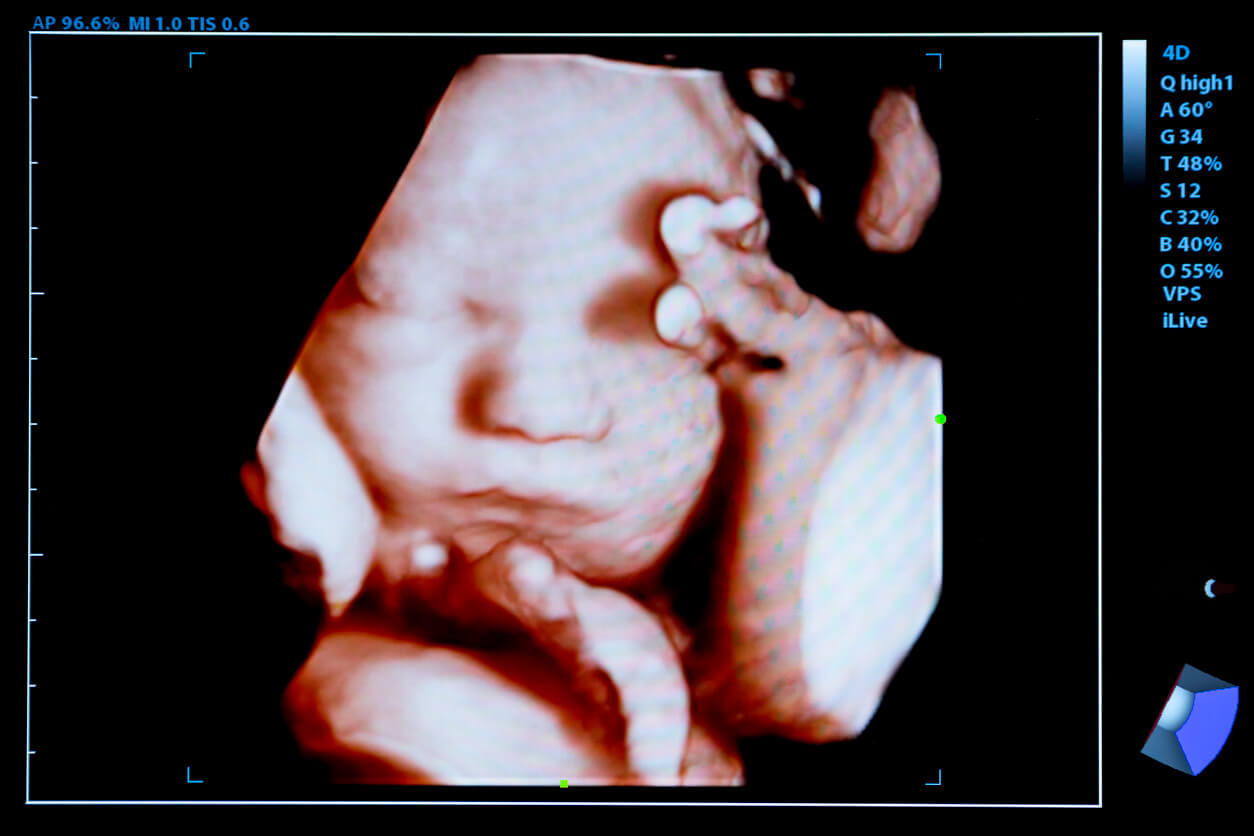

L’échographie 4D est un nouveau test de diagnostic qui permet d’obtenir des images détaillées du fœtus grâce à des ondes ultrasonores à haute fréquence. Contrairement aux précédents, il parvient à reproduire environ 24 images 3D en une seconde et leur donne du mouvement.

Par ailleurs, en plus d’un examen détaillé du corps de l’enfant, vous pouvez voir quelques grimaces qu’il fait. Comme sourire, sucer son pouce ou bâiller.